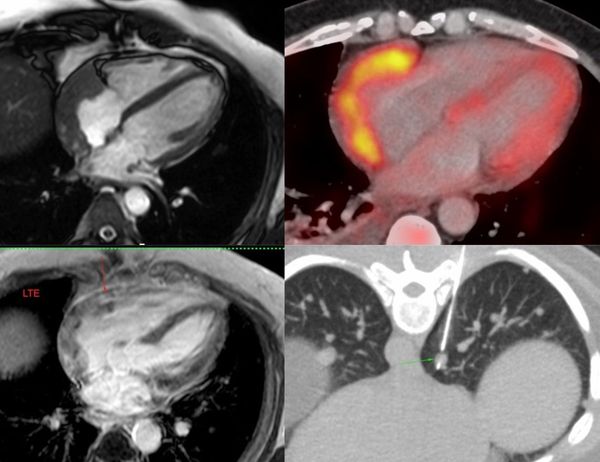

Multiparametric mapping and CT scan help in the diagnosis of cardiac masses